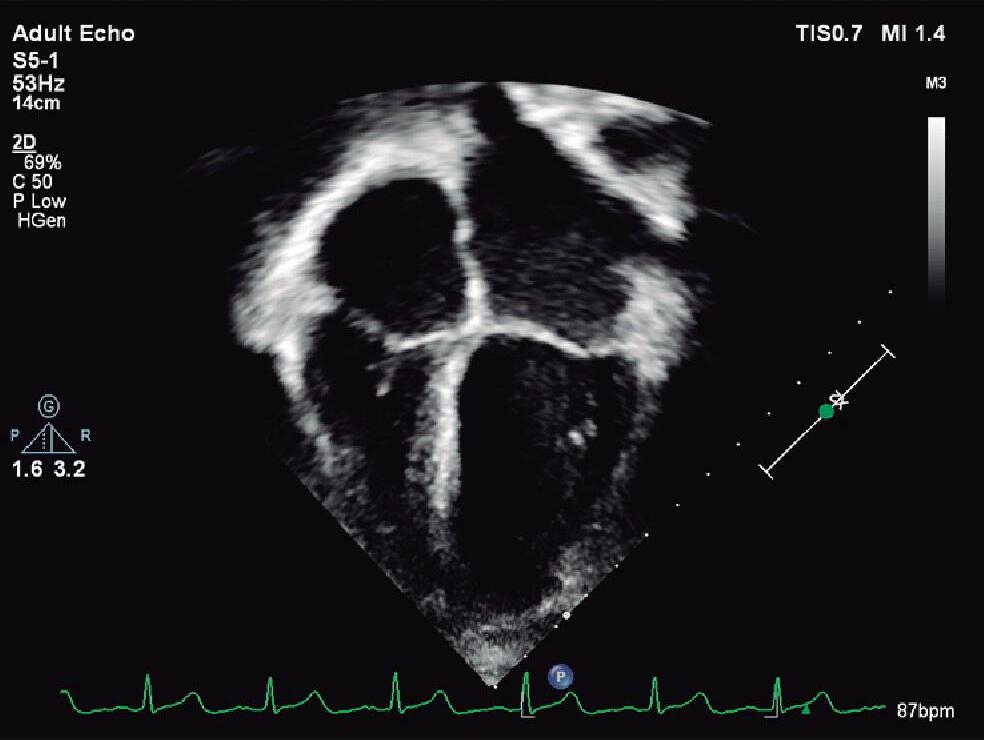

O plano apical (4 e 5 câmaras e longo eixo: 2 e 3 câmaras) é obtido posicionando-se o transdutor no tórax do paciente na região onde o ictus do VE pode ser palpado e com o index voltado para a axila esquerda do paciente. Quando possível, objetivando melhor qualidade da imagem a ser obtida em crianças maiores ou adolescentes, o semidecúbito lateral esquerdo com o membro superior esquerdo elevado é a posição ideal na maioria dos exames (▶ Vídeo 1-24).

Em geral, iniciamos pelo plano apical 4 câmaras (visão posterior) e movimentamos, em direção posterior, o transdutor (posição equivalente às 2 ou 3 horas num relógio) (Fig. 1-5c e ▶ Vídeo 1-25), sendo possível avaliar: o átrio direito detalhando a entrada da veia cava inferior no AD e o seio coronário (Fig. 1-9a e ▶ Vídeo 1-26), o AE com veias pulmonares e a aorta torácica descendente próxima a esse átrio, o septo interventricular e os ventrículos com seus respectivos músculos papilares e de suas vias de entrada (valvas mitral e tricúspide) (Fig. 1-9b e ▶ Vídeo 1-27). Nessa avaliação, o Doppler colorido deve ser cuidadosamente utilizado na “busca” de comunicações interventriculares particularmente no septo muscular apical (Fig. 1-9c e ▶ Vídeo 1-28). Entretanto, não é indicado para a avaliação do septo interatrial, pois, devido à posição paralela do feixe do ultrassom, pode gerar uma falsa comunicação. Os recursos de Doppler pulsado e colorido são importantes na avaliação da função das valvas AVs e de obstruções ao fluxo, como membrana supravalvar mitral ou banda anômala do VD.

Fig. 1-9. Plano apical: (a) seio coronário, (b) 4 câmaras e (c) 4 câmaras com Doppler colorido. AD: átrio direito; AE: átrio esquerdo; VD: ventrículo direito; VE: ventrículo esquerdo; SC: seio coronário; M; valva mitral; T: valva tricúspide.